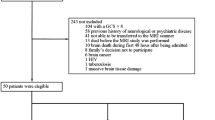

The cohort included 69 patients with SAH, with patient selection summarized in Fig. 2. Baseline characteristics are summarized in Table 1. Seventy percent of patients were female, and the mean age was 58 years (± 15.7). EEG was performed at a median of 3 days after SAH diagnosis, with an interquartile range of 2–8 days. Follow-up examinations occurred at a median of 4 months (interquartile range 2–6) from admission. Mortality was 17.4%; 11 of 12 deaths occurred during the initial hospitalization, and 9 of 12 deaths occurred in the setting of withdrawal of life-sustaining therapies.